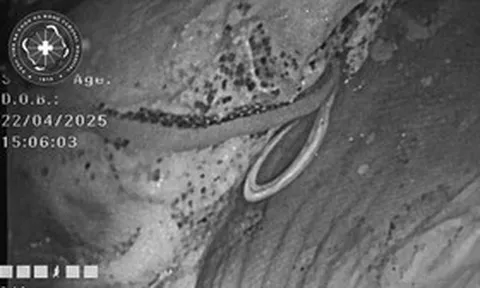

Điều đáng nói đằng sau vẻ ngoài khỏe mạnh ấy lại là một diễn biến bệnh lý âm thầm. Ông Trương nhập viện trong tình trạng nặng, các bác sĩ xác định chức năng thận của ông đã suy kiệt nghiêm trọng, không còn khả năng hồi phục.

Người đàn ông 62 tuổi tử vong vì suy thận giai đoạn cuối. Ảnh minh họa.

Theo người thân, ông Trương-giáo viên nghỉ hưu 62 tuổi, từng được cả khu phố ngưỡng mộ vì lối sống “chuẩn mực” đã không qua khỏi do suy thận giai đoạn cuối. Sự ra đi của ông khiến gia đình bàng hoàng: vì sao một người ngủ sớm, dậy sớm, chăm tập thể dục lại có thể gục ngã nhanh đến vậy?

Theo chuyên gia, thói quen uống trà đặc mỗi ngày chính là “thủ phạm” hàng đầu. Trà đặc chứa hàm lượng caffeine và theophylline cao, khiến thận phải làm việc liên tục để đào thải, lâu dài gây tổn hại chức năng thận.